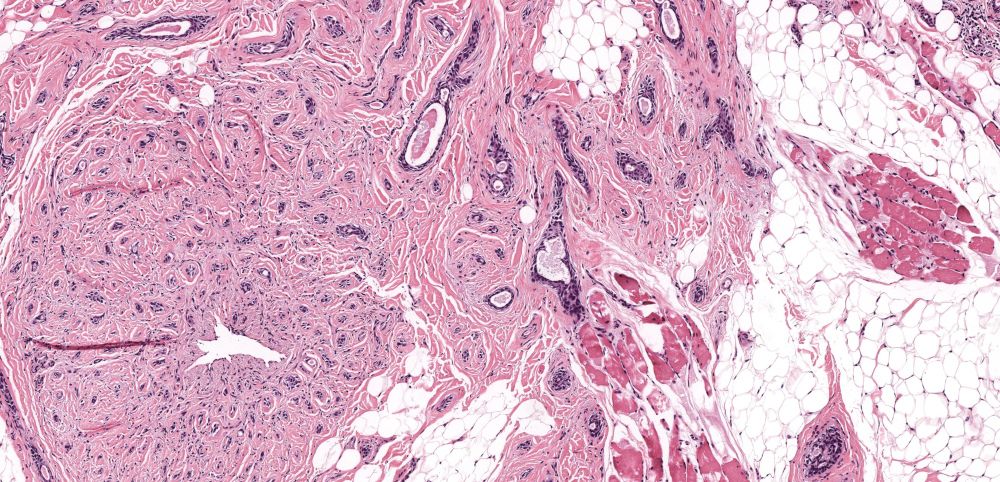

T-cell Tuesday

71M presents with red patches on legs which generalized over 2 yrs. Initially responded to tx followed by presentation 2 yrs later with multiple nodules distributed over his body. Here is a right axilla punch biopsy.

Your diagnosis? Which stains would you like to see?